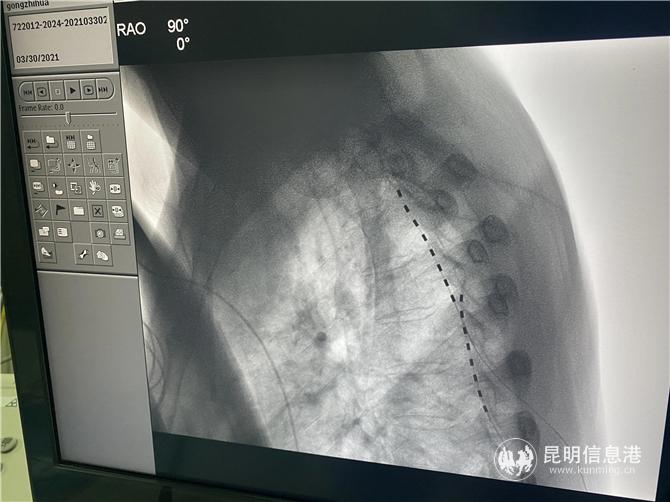

2021年2月,龔志華入院,龔會軍詳細(xì)詢問了病史,反復(fù)評估,聽取科內(nèi)的討論和外省專家的意見,結(jié)合病癥,診斷為復(fù)雜性局部痛綜合征(CRPS),但因疼痛范圍較廣、疼痛區(qū)域變化、疼痛時間較長,加之,患者由于多次手術(shù),脊柱椎管等解剖結(jié)構(gòu)嚴(yán)重改變并粘連,在手術(shù)方案的選擇上帶來了難度。經(jīng)科內(nèi)反復(fù)討論病例,決定用脊髓鞘內(nèi)注嗎啡和安置脊髓電刺激兩種新技術(shù)來比較療效,最終一致決定采用創(chuàng)傷心主任朱曉松教授意見,采用脊髓電極置入術(shù)進(jìn)行治療。

3月31日,在多學(xué)科團(tuán)隊(duì)的配合下,龔會軍在介入雜交手術(shù)室、用局麻下為患者植入電極,由于患者之前的陳舊性損傷,患者的脊柱結(jié)構(gòu)黏黏嚴(yán)重,給上行穿刺造成了極大的困難,同時,術(shù)中患者的疼痛位置又發(fā)生了變化,龔會軍團(tuán)隊(duì)及時調(diào)整,術(shù)中測試患者疼痛區(qū)域全覆蓋。術(shù)后,龔志華的疼痛明顯緩解。(昆明信息港 記者孫紅亮)